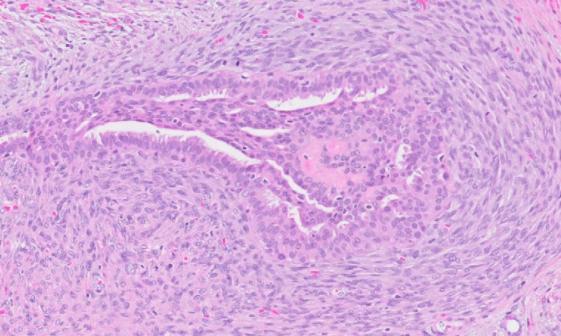

交界性叶状肿瘤:交界性叶状肿瘤是介于良性叶状肿瘤和恶性叶状肿瘤之间的一种类型。其生物学行为和组织学特征介于良性和恶性之间,具有一定的侵袭性,但转移能力较弱。手术后需要密切随访,以防复发或恶变。

交界性叶状肿瘤镜下影像